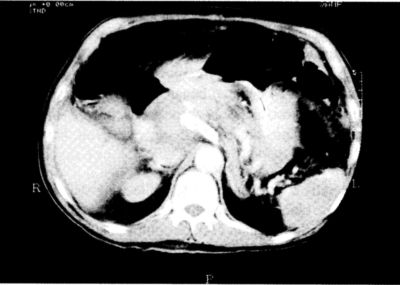

3. ábra.

2 cm-rel distalisabb síkban készült CT-felvétel az aorta előtt szembetűnő a meszes, tágult truncus coeliacus (fehér), ettől jobbra (a felvételen balra) a thrombussal kitöltött álaneurysma.